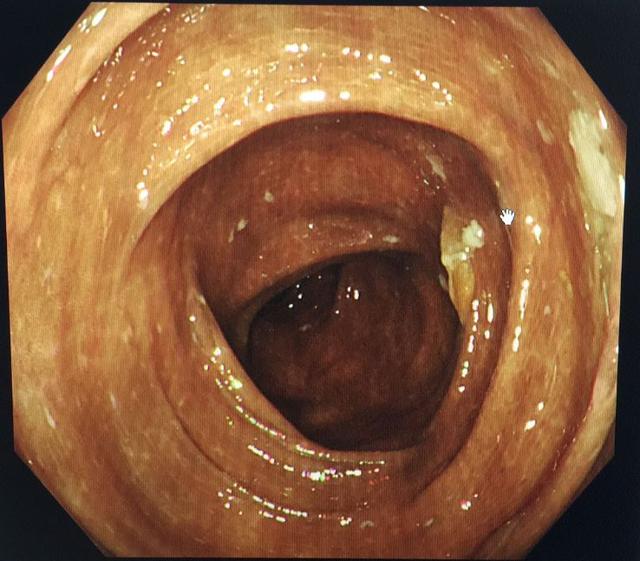

结肠病

结肠黑变病

图片尺寸640x557

可怕的结肠黑变病_肠疾病_肠疾病相关疾病 - 好大夫在线